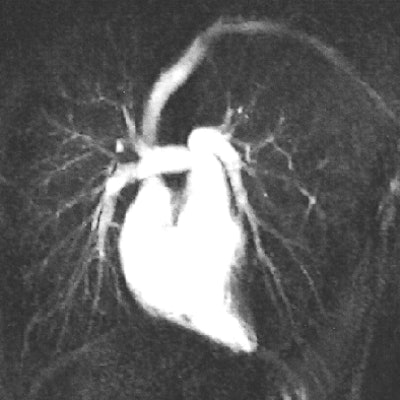

| Fig. A (above), 23-year-old woman referred to MRI with suspicion of transposition of great arteries because of prominent trabeculation of subaortic ventricle in echocardiography. Time-resolved coronal maximum-intensity-projection angiograms (B-C, below) and cine short-axis view (D, bottom). The angiograms show normal time course of enhancement of subpulmonary atrium and ventricle and pulmonary arteries (A); and enhancement of pulmonary veins, subaortic atrium, ventricle, and aorta (B). Note decreasing enhancement of subpulmonary ventricle from A to C, indicating absence of relevant left-to-right shunt flow. This patient suffered from noncompaction myocardium, which is visualized on time-resolved MR angiography (C) (arrow) and is shown on cine short-axis view (D) (arrows). Republished with permission of the American Roentgen Ray Society from AJR 2006; 187:1107-1114. |